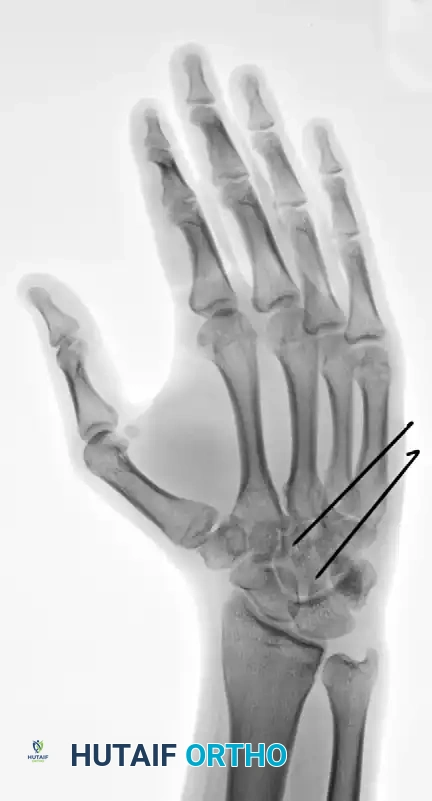

Standard posteroanterior (PA), lateral, and oblique radiographs are mandatory. However, the overlapping anatomy of the carpus can obscure subtle subluxations.

FIGURE 67-30 B-D: Posteroanterior, Lateral, and Oblique radiographic views demonstrating the dorsal dislocation of the fourth and fifth carpometacarpal joints.

> CLINICAL PEARL: Always obtain a true lateral radiograph of the hand. The metacarpal shafts should align perfectly parallel. Any dorsal divergence of the 4th or 5th metacarpal shafts relative to the 3rd metacarpal is highly indicative of a CMC dislocation. If plain films are equivocal, a CT scan is the gold standard for evaluating articular comminution and subluxation.

FIGURE 67-29 A-C: Preoperative radiographs of a small finger carpometacarpal fracture-subluxation in a 34-year-old man, demonstrating dorsal displacement and articular incongruity.